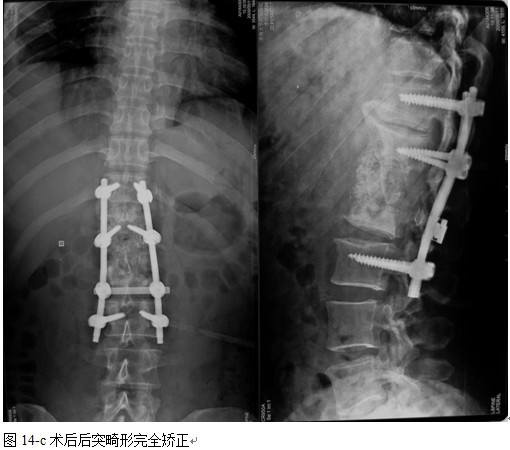

结果: 术后所有患者均显示,骨性融合, 马尾神经损伤的患者均基本恢复正常,术后后凸畸形平均矫正90%以上, 3-49个月的随访,后凸角度平均丢失4.2°。

本组手术用时间3~4h , 平均3.5h 。术中出血300~500ml , 平均约350ml 。术后症状完全缓解,无神经功能障碍加重等并发症,1例营养差的老年患者伤口出现窦道,1例因肝功能差,术后未口服抗痨药,伤口出现窦道,经换药后二期愈合,其余病例伤口均一期愈合。马尾神经受损的患者术后基本恢复正常。术后一周后凸角平均 5.4°后凸畸形平均矫正90%以上, 最终后凸角平均8.3°,后凸角度平均丢失4.2°。随访3个月有87%(40/46)有骨痂形成,6个月91.3%(42/46)明显骨性愈合(见图),其余4例9-12个月内愈合,随访时间3-32个月,平均11个月,46例患者中2例在术后2个月和3个月时背部形成脓肿,换药后治愈。2例出院1月后并发结核性脑膜炎,治疗后好转。1例因椎弓根钉偏外,刺激神经根,5个月后从侧方脱出,疼痛加重,因前后路植骨完全愈合,取出后症状完全缓解。

中国学者金大地[22]等采用一期前路病灶清除植骨前路钢板固定治疗腰椎结核,平均18°的后凸畸形得以矫正,Mukhtar[23] AM等采用前路病灶清除植骨分期或同期后路固定治疗腰椎结核22例,术后后凸畸形矫正度数平均为27°。从我们的随访结果看,术后后凸畸形平均矫正度数为26.9°,后凸畸形平均矫正90%以上, 6个月-49个月后随访,后凸角度平均丢失4.2°。本术式也适用于结核所引起的弹性差的后凸畸形,对于病灶纤维化或骨化的非弹性后凸畸形,后路固定后,先行前路病灶、纤维化或骨化切除、松解,逐步刮除病灶、逐步撑开,达到畸形矫正和植骨的目的。